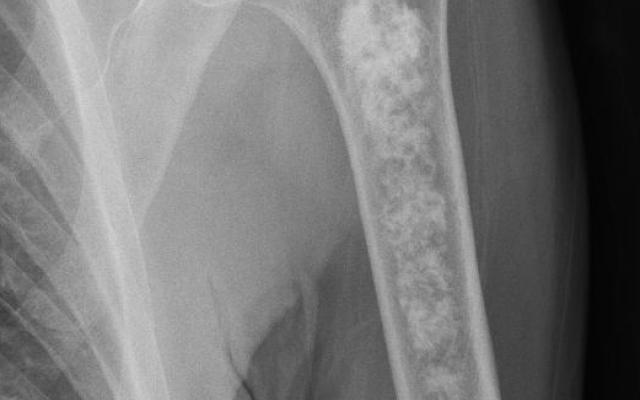

Dit artikel is alleen beschikbaar als PDF.Lees de PDF Artikelinformatie Online verschenen op 24 juni 1950 Citeer dit artikel als Ned Tijdschr Geneeskd. 1950;94:2957-63 Heb je nog vragen na het lezen van dit artikel? Check onze AI-tool en verbaas je over de antwoorden. ASK NTVG Ook interessant Nieuws Meer afwijkingen in het bovenste deel van het maag-darmkanaal dan in het colon bij positieve benzidinereactie van de feces Diagnose in beeld Een man met een afwijkende bovenarm op de X-thorax Beeldquiz Een man met een afwijkende bovenarm op de X-thorax Meer gerelateerd … Reacties Login om een reactie te plaatsen